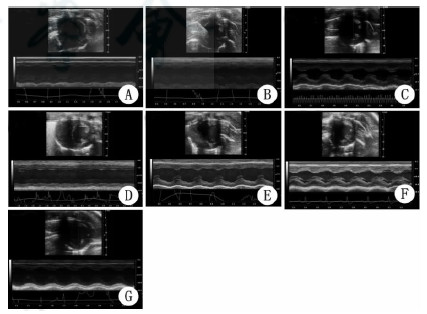

不同组不同时期心脏彩超如图 2所示。

| A:窒息组4 h;B:窒息组24 h;C:窒息组72 h;D:室颤组4 h;E:室颤组24 h;F:室颤组72 h;G:假手术组 图 2 各组心脏彩超图片 Fig 2 The echocardiography of each groups |

如表 1所示,EF(%)窒息组不同时间点不全相同,4 h与假手术组差异有统计学意义(LSD-t=17.630,P < 0.01),24 h与假手术组差异有统计学意义(LSD-t=4.450,P=0.048),72 h与假手术组间差异有统计学意义(LSD-t=6.242,P=0.017);室颤组不同时间点EF不全相同,4 h与假手术组差异有统计学意义(LSD-t=25.099,P < 0.01),24 h与假手术组差异无统计学意义(LSD-t=1.989,P=0.118),72 h与假手术组差异有统计学意义(LSD-t=4.748,P=0.040);窒息组与室颤组4 h组间差异有统计学意义(t=5.584,P=0.031),而两组24 h组间(t=0.421,P=0.695)、72 h组间差异无统计学意义(t=1.016,P=0.399)。

舒张期LVAWd(mm)窒息组不同时间点不全相同,其中4 h、24 h与假手术组差异无统计学意义,72 h与假手术组差异有统计学意义(LSD-t=8.062,P=0.007),72 h与4 h差异有统计学意义(LSD-t=9.978,P=0.003);而室颤组不同时间点LVAWd不全相同,其中72 h与假手术组差异有统计学意义(LSD-t=6.682,P=0.013),4 h与72 h差异有统计学意义(LSD-t=3.027,P=0.049),其余4 h、24 h、假手术组差异无统计学意义;舒张期左室前壁厚度窒息组与室颤组在相同时间点差异无统计学意义,见表 1。

3 讨论 3.1 复苏后早期不同模型心脏损伤和功能变化本研究心肌组织HE染色图片可观察到4 h时室颤及窒息模型都有心肌损伤,室颤组肌溶解明显。线粒体是细胞能量代谢的场所,再灌注期线粒体氧化磷酸化功能异常,产生大量活性氧,损伤线粒体呼吸链结构,使线粒体氧化磷酸化功能下降[2, 10]。RCR初步提示线粒体呼吸功能,从能量代谢能力方面评价心肌损伤及修复情况,两种模型RCR显示心肌线粒体呼吸功能受损。与此类似,心脏彩超提示两组的心脏左室射血分数下降,以上均提示在复苏后早期两种复苏模型的心肌损伤严重,心功能下降。这与Tang等[4]等发现大鼠复苏后心肌的收缩功能和左室顺应性下降,Gazmuri等[5]发现猪复苏后左室射血分数下降,每搏输出量和心脏做功指数下降,所提示的心肺复苏后早期即出现严重心功能不全的结果相符。然而Wu等[9]在猪8 min心搏骤停窒息法和室颤法复苏模型的比较中提出,在复苏后早期窒息模型心肌超微结构损害及凋亡较室颤模型严重;Tsai等[7]在大鼠5 min心搏骤停复苏模型的对比中亦提出在复苏后早期窒息模型出现弥漫性心肌损伤;而本研究心脏彩超结果却显示,复苏后早期室颤模型心功能较窒息模型差(EF减小)。考虑与室颤模型在电流刺激下发生严重的心电紊乱导致心搏骤停和心脏供血的突然中断,在再灌注时期可能发生心肌顿抑[11]有关,心肌顿抑虽然无心肌坏死,但在心脏血流恢复之后心功能障碍却无法立即恢复[11],导致暂时性的心功能恶化。

3.2 复苏中后期不同模型心脏损伤的修复和功能的变化随着生存时间的延长,两种模型的心功能均有所恢复,并且室颤组的EF较窒息组的更早恢复,这一结果亦支持室颤模型发生心肌顿抑的假设,同时窒息模型的缺氧时间较室颤模型长,心肌弥漫性损伤及超微结构损伤可能较室颤模型严重[7, 9, 12],导致心肌的损伤修复过程更长,因此心功能恢复更慢。

在后期,两种复苏模型心脏大体可见心肌向心性肥厚,光镜下所见的心肌细胞排列紊乱,同时心脏彩超也显示模型组在恢复期左室前壁厚度增加,提示无论是心源性还是呼吸源性心搏骤停复苏成功后,均存在心肌细胞损伤、心肌重构的可能。室颤组在72 h心脏射血分数及线粒体呼吸功能均较对照组增强,窒息组72 h心脏射血分数较假手术组增加,结合实验组左室前壁厚度增加,均提示恢复期(24~72 h)处于心肌重构代偿期,这也与心肌重构在代偿期有改善心功能的作用[13]的情况相符。心肌重构的过程中心肌细胞由正常心肌细胞向胎儿类型心肌细胞转化,这种心肌细胞能耗低,肌肉最大缩短速度和张力发展速度缓慢,不能满足长期高效工作需要,最后导致心肌收缩功能下降[14]。心力衰竭是各种心脏病的临床终末阶段,20世纪90年中期开始认识到导致慢性心衰的共同的病理生理基础是心肌重构[13]。